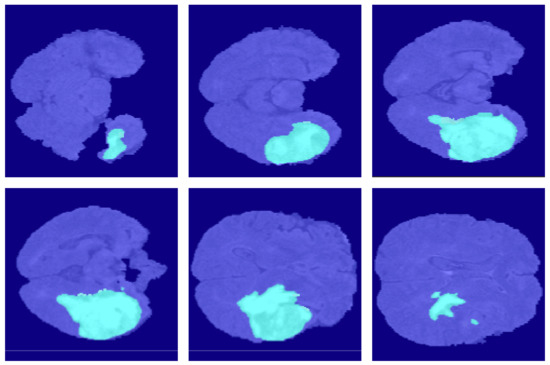

4.2. Segmentation Results

5.3. Ablation Experiment of Pruning Mechanism